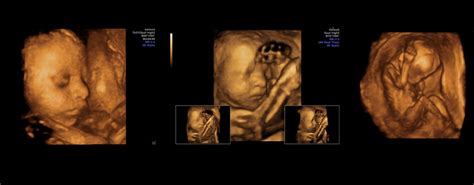

Morfologia fetală reprezintă o ecografie detaliată, efectuată de obicei în trimestrul al doilea de sarcină, cu scopul de a evalua dezvoltarea anatomică a fătului. Această investigație permite medicilor să identifice eventuale anomalii sau malformații congenitale, oferind părinților liniștea necesară sau posibilitatea de a pregăti din timp managementul medical post-natal.

Diagnosticul ecografic în anomaliile fetale este un domeniu de o importanță deosebită, iar abordarea interdisciplinară, alături de importanța autopsiei perinatale, contribuie la o înțelegere completă a stării de sănătate a fătului.